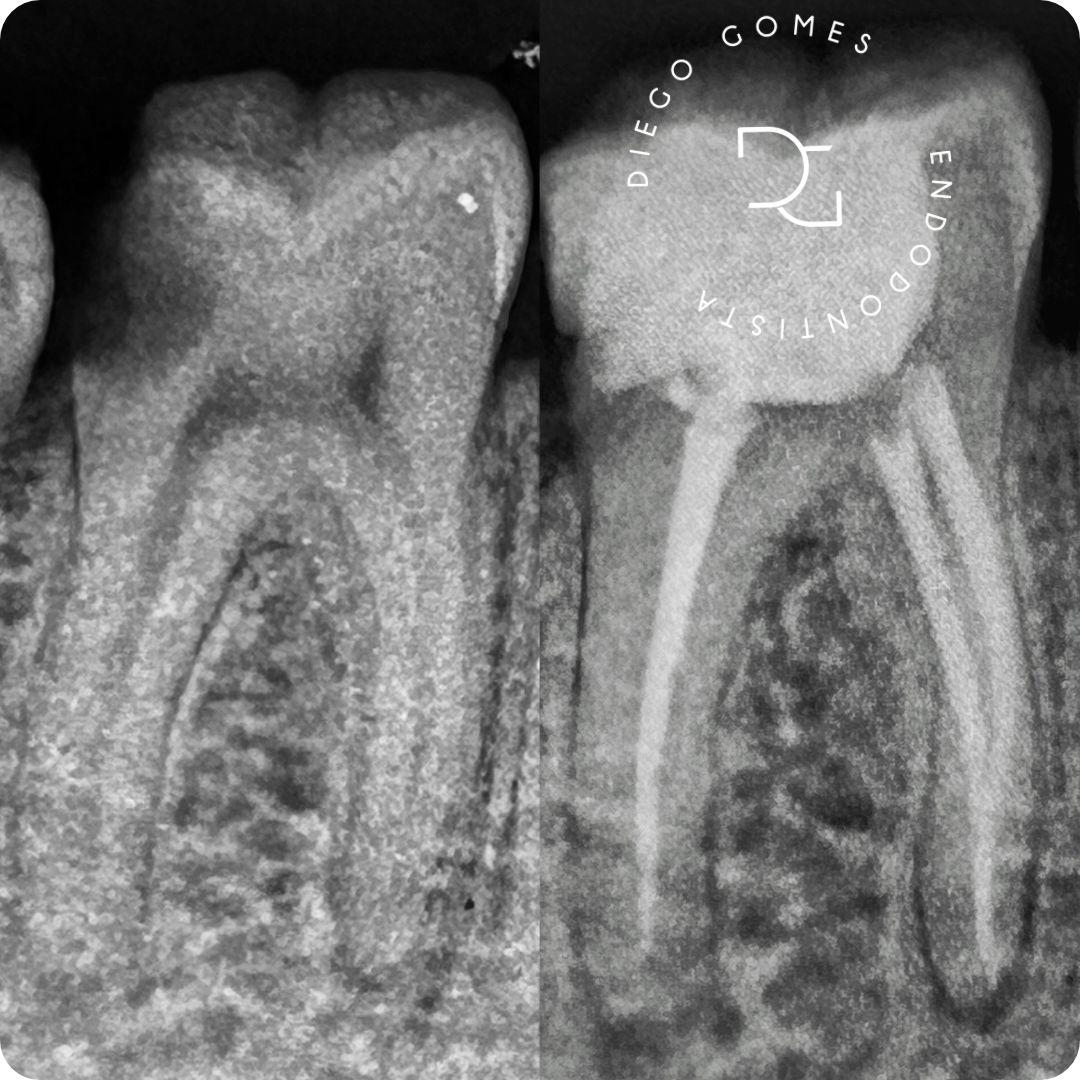

● Tratamento e retratamento de canal

● Tratamento de reabsorção